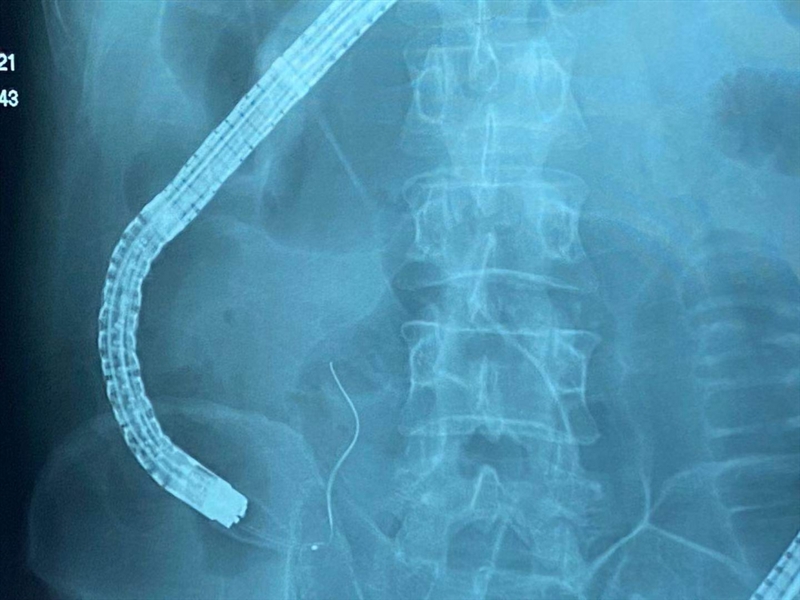

2.内镜逆行性阑尾造影术:X线下,阑尾腔内注入造影剂显示阑尾腔的形态,如有粪石,则行球囊取石术。并确认有无阑尾穿孔。

4.塑料支架置入及脓液引流:在充分取出粪石后,置入塑料支架行脓液引流及进一步阑尾腔冲洗(生理盐水+抗生素),X线下查看阑尾腔内支架的位置及形态,放置的支架于术后四周左右肠镜下取出,大多数会自动脱落排出。